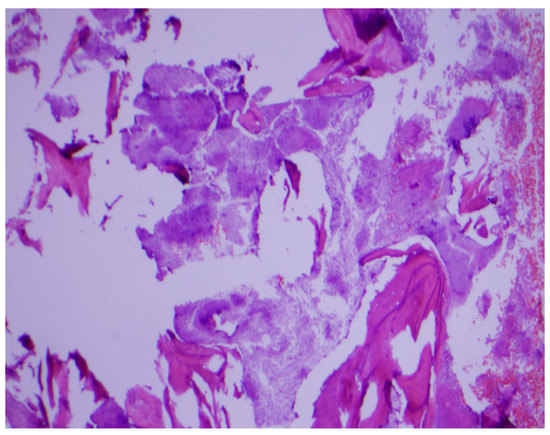

Histopathological examination of the mandibular bone showed osteonecrosis, sulfur granules and embedded organisms on hematoxylin and eosin (H&E) stain (Figure 3 and Figure 4), which were better characterized on Gomori-Grocott methenamine silver stain (GMS) as multiple branching organisms (Figure 5). The official histopathology report read, “acute and chronic osteomyelitis with Actinomyces-like organisms”. A diagnosis of actinomycosis was made, following which the patient was desensitized and treated with intravenous penicillin G for two weeks, followed by oral penicillin VK for six months. He made a complete recovery at the end of therapy with total resolution of symptoms and closure of the exposed bone.

Figure 3.

Osteonecrosis of the jaw on hematoxylin and eosin stain. Original magnification ×40.

Figure 4.

Sulfur granule (arrow) showing embedded organisms on H&E stain. Original magnification ×200.